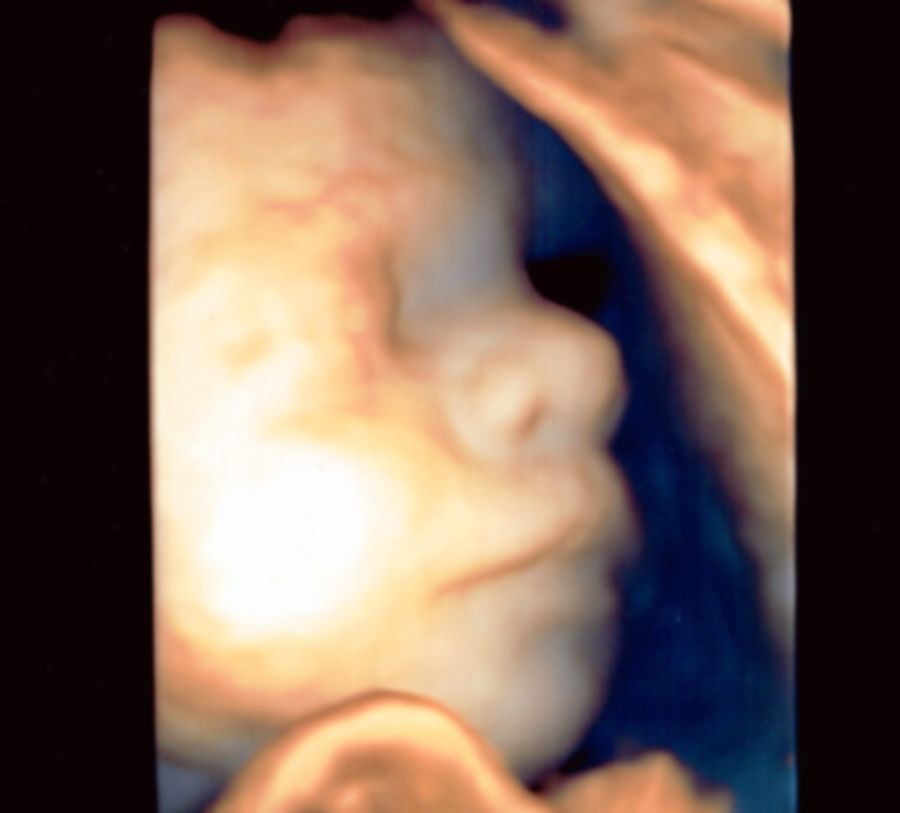

Moją pasją jest diagnostyka ultrasonograficzna w ginekologii i położnictwie, ocena anatomii płodu w badaniach prenatalnych. Nieustająco podnoszę kwalifikacje celem zapewnienia pacjentowi najlepszej opieki. Posiadam certyfikaty Polskiego Towarzystwa Ginekologów i Położników, Polskiego Towarzystwa Ultrasonografii oraz Fetal Medicine Foundation do wykonywania badań ultrasonograficznych.